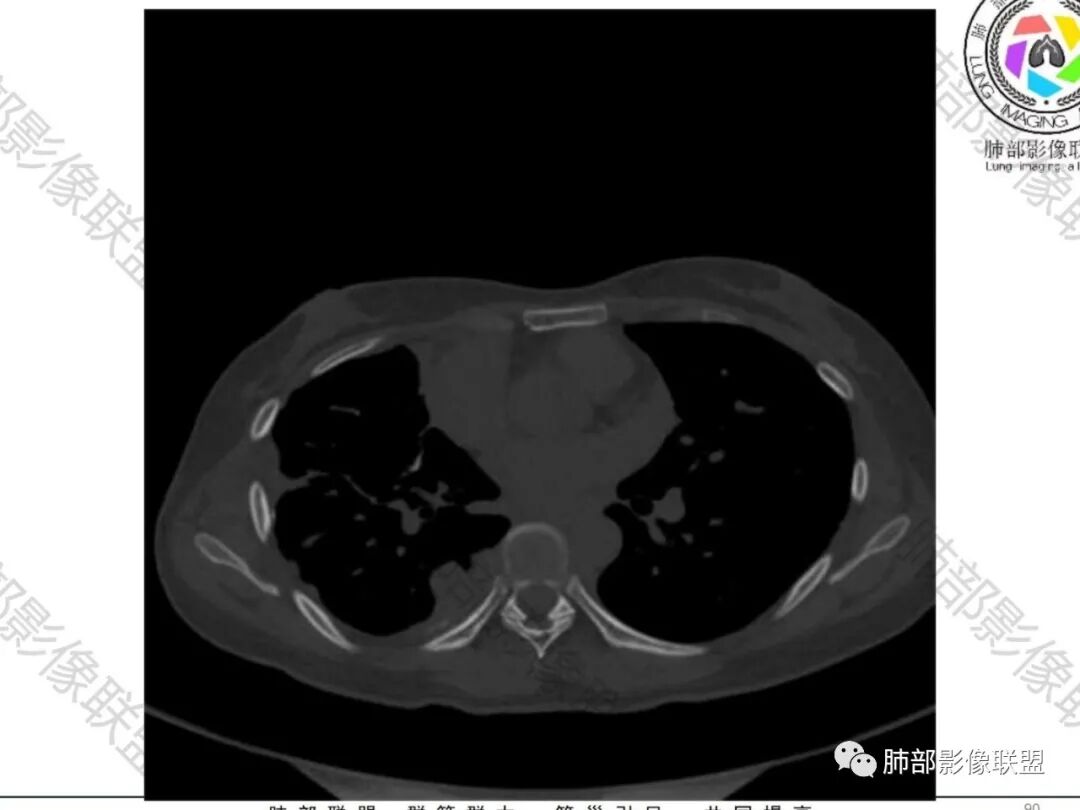

一切∮随缘:双侧胸廓塌陷,以右侧为主,右侧肋间隙狭窄,双肺上叶及右肺下叶胸膜下多发不规则肿块,密度不均匀,内部可见条片状,不规则钙化影,部分钙化不密实,双肺多发纤维索条影,似陈旧性病灶,双侧胸水,临床年轻女性,无感染症状,考虑考虑结核淀粉样变,转移性钙化,弥漫性肺骨化病。

王秀仙:双肺多发条索状及结节状病灶,部分钙化,边界清晰,双侧纵膈胸膜及双侧胸膜可见结块状及弧形软组织肿块,内见多发钙化灶,右侧胸腔塌陷,考虑结核伴淀粉样变性。鉴别胸膜间皮瘤。

丽:双肺散在索条及条片状高密度影,边界清晰,部分实变内可见钙化,支气管管壁增厚,双肺胸膜局限性增厚伴钙化,部分肋骨密度增高,首先考虑结核并淀粉样变性,鉴别转移性钙化,肿瘤样钙质沉着症,胸膜间皮瘤。

尘缘:青年女性,痰中带血,胸痛2月,无发热盗汗,实验室检查,有贫血,总蛋白降低,血沉情况未知,肿标基本正常。影像表现:双上肺小叶间隔增厚,双侧胸膜广泛不规则增厚,胸膜下多发肿块伴不规则钙化,右侧肋骨破坏。纵隔淋巴结肿大不明显,双肺门淋巴结肿大,部分融合,分析思路:一、感染性病变,1、结核,青年女性,胸膜增厚,多发肿块伴钙化,有咳嗽胸痛,痰中带血,要考虑,但无结核中毒症状,病史仅两月却钙化太明显,肺内没有明显树芽征,存疑,2、其他感染,无炎性指标支持,白细胞不高,可能性小。二、非感染性病变,1、尘肺,胸膜增厚,钙化,胸膜下钙化性肿块,要考虑,但肺内无粉尘结节,无职业史,可能小。2、转移性钙化,无肾脏病史,无血清钙磷代谢异常指标支持,肺内间质无钙沉积改变,基本排除。三、肿瘤性病变,1、肺癌伴转移,双上肺有小叶间隔增厚,双肺门有淋巴结肿大,要考虑,但青年女性,病史两月,钙化太多太广泛,肿标基本正常,可能性小。2、骨肉瘤转移。15-30岁青年人,是骨肉瘤高发年龄,肺内多发成骨样钙化转移灶,双上肺小叶间隔增厚符合癌淋样表现,右侧肋骨破坏,要高度怀疑,需要详细询问病史及手术史。3、软骨来源肿瘤伴肺内转移,右侧肋骨虽有破坏,但无明显软骨样破坏及钙化。可能小。4、其他肿瘤伴转移,青年女性,其他恶性肿瘤能广泛发生钙化性转移的可能性小。综上所述:骨肉瘤伴右侧肋骨及胸膜转移,胸膜下转移,肺内癌淋可能最大,结核不完全除外,下一步需要,仔细询问病史,如果有骨肉瘤史,则基本确诊,如果没有,需要进一步问询呼吸系统症状,病程,以前的影像对照,了解肾脏情况,查血清钙磷指标。

淀粉样变符合吗?也不符合。如果是淀粉样变,一般这么弥漫的钙化,肺门淋巴结都应该有钙化,而且侵袭性及肋骨表现都不支持淀粉样变性。